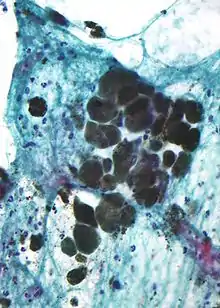

Melanin is brown, non-refractile, and finely granular with individual granules having a diameter of less than 800 nanometers. This differentiates melanin from common blood breakdown pigments, which are larger, chunky, and refractile, and range in color from green to yellow or red-brown. In heavily pigmented lesions, dense aggregates of melanin can obscure histologic detail. A dilute solution of potassium permanganate is an effective melanin bleach.[54]